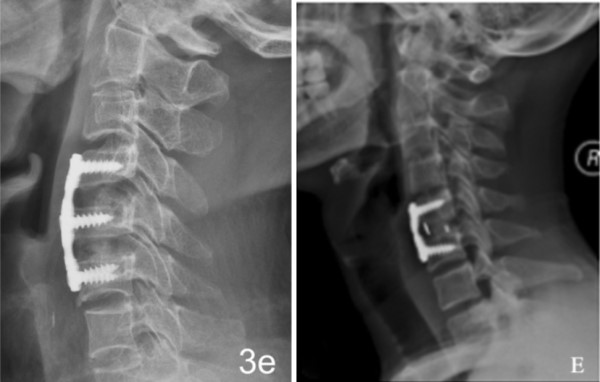

相关产品

Related Products